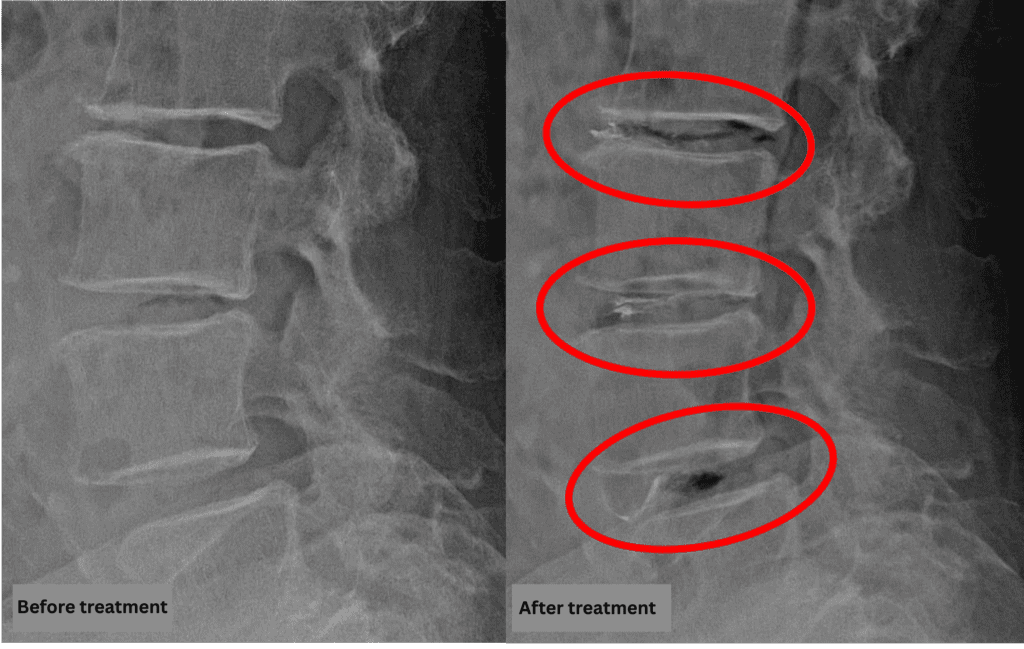

• L2/3: Disc degeneration, bulging, foraminal stenosis

• L3/4: Disc degeneration, bulging, foraminal stenosis, spinal canal stenosis

• L4/5: Disc degeneration, bulging, foraminal stenosis, spinal canal stenosis, degenerative spondylolisthesis

• L5/S1: Disc degeneration, bone fusion

The above findings were also observed on the imaging.

Compression of the spinal canal due to disc pathology at L2/3, L3/4, and L4/5 is highly likely the cause of symptoms.

After consulting with the patient, the Cellgel Method was performed on L2/3, 3/4 and 4/5.